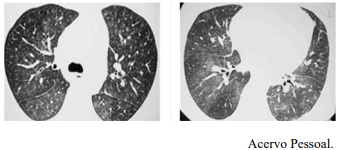

Um Paciente de 25 anos de idade, com tosse e febre de início súbitos 60 dias após transplante de medula óssea, realizou RT-PCR para Covid-19, cujo resultado foi negativo. Constataram-se exame de BAAR negativo, teste de Mantoux negativo e fibrobroncoscopia com cultura e BAAR negativos. A tomografia de tórax apresenta opacidades com atenuação em vidro fosco e pequenos nódulos pulmonares bilaterais, conforme as imagens a seguir.

Considerando esse caso clínico, as imagens apresentadas e os conhecimentos médicos correlatos, julgue o item a seguir.

Citomegalovírus em paciente imunocomprometido é uma das possibilidades diagnósticas.